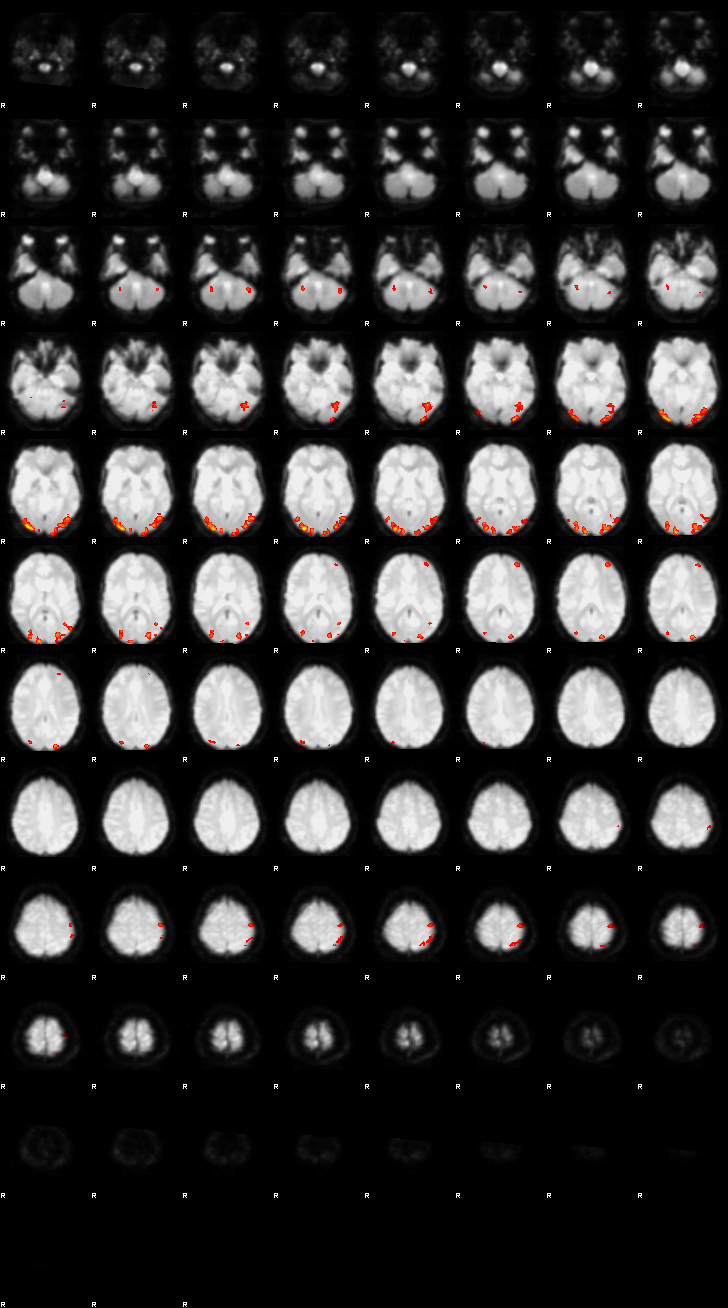

Let’s now display the thresholded activation maps. A voxelwise threshold of Z > 3.1 was applied, followed by cluster-level correction at p < 0.05 (corrected for multiple comparisons).

zstat1 - C1 (incongruent)

zstat2 - C2 (congruent)

zstat3 - C3 (incongruent-congruent)

display(Markdown("#### Incongruent"), rendered_thresh_zstats1)

Incongruent

display(Markdown("#### Congruent"), rendered_thresh_zstats2)

Congruent

display(Markdown("#### Incongruent-Congruent"), rendered_thresh_zstats3)

Incongruent-Congruent